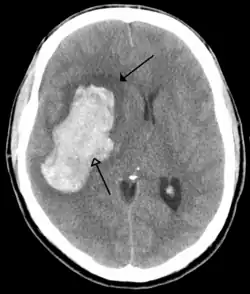

Tumours

Brain tumours can be either benign or cancerous. Most malignant tumours arise from another part of the body, most commonly from the lung, breast and skin.[178] Cancers of brain tissue can also occur, and originate from any tissue in and around the brain. Meningioma, cancer of the meninges around the brain, is more common than cancers of brain tissue.[178] Cancers within the brain may cause symptoms related to their size or position, with symptoms including headache and nausea, or the gradual development of focal symptoms such as gradual difficulty seeing, swallowing, talking, or as a change of mood.[178] Cancers are in general investigated through the use of CT scans and MRI scans. A variety of other tests including blood tests and lumbar puncture may be used to investigate for the cause of the cancer and evaluate the type and stage of the cancer.[178] The corticosteroid dexamethasone is often given to decrease the swelling of brain tissue around a tumour. Surgery may be considered, however given the complex nature of many tumours or based on tumour stage or type, radiotherapy or chemotherapy may be considered more suitable.[178]